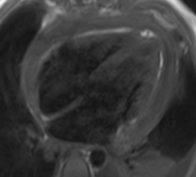

Diagnostic Techniques and Their Most Important Findings: Chest CT revealed bilateral small pleural effusions, significant pericardial effusion, and minimal ascites. Transthoracic echocardiogram showed moderate-to-large pericardial effusion without hemodynamic compromise. Cardiac Magnetic Resonance Imaging (CMR) demonstrated pericardial thickening, enhancement of the pericardial leaflets, and mild-to-moderate exudative pericardial effusion suggestive of pericarditis. Due to high suspicion of tuberculous etiology, pericardiocentesis followed by surgical pericardiotomy was performed. Although pericardial fluid analysis was nonspecific and negative for acid-fast bacilli, pericardial biopsy confirmed granulomas with caseous necrosis. Anti-tuberculosis therapy was started with subsequent clinical improvement.

Learning Points from this Case: Concato’s polyserositis is a rare but severe manifestation of extrapulmonary tuberculosis, particularly in children. Diagnosis requires a high index of suspicion, especially in endemic areas, and imaging plays a central role. In this case, CMR findings were instrumental in guiding invasive diagnostic procedures. While pericardial fluid analysis may be inconclusive, histopathological examination remains essential for definitive diagnosis. Early recognition and appropriate treatment of tuberculous pericarditis can prevent complications such as constrictive pericarditis and improve outcomes.

Pericardial enhancement

Pericardial enhancement

Diagnostic Techniques and Their Most Important Findings: Chest CT revealed bilateral small pleural effusions, significant pericardial effusion, and minimal ascites. Transthoracic echocardiogram showed moderate-to-large pericardial effusion without hemodynamic compromise. Cardiac Magnetic Resonance Imaging (CMR) demonstrated pericardial thickening, enhancement of the pericardial leaflets, and mild-to-moderate exudative pericardial effusion suggestive of pericarditis. Due to high suspicion of tuberculous etiology, pericardiocentesis followed by surgical pericardiotomy was performed. Although pericardial fluid analysis was nonspecific and negative for acid-fast bacilli, pericardial biopsy confirmed granulomas with caseous necrosis. Anti-tuberculosis therapy was started with subsequent clinical improvement.

Learning Points from this Case: Concato’s polyserositis is a rare but severe manifestation of extrapulmonary tuberculosis, particularly in children. Diagnosis requires a high index of suspicion, especially in endemic areas, and imaging plays a central role. In this case, CMR findings were instrumental in guiding invasive diagnostic procedures. While pericardial fluid analysis may be inconclusive, histopathological examination remains essential for definitive diagnosis. Early recognition and appropriate treatment of tuberculous pericarditis can prevent complications such as constrictive pericarditis and improve outcomes.

Pericardial enhancement